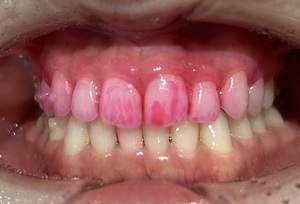

治療前

治療後

| 年齢 | 23歳・女性 |

|---|---|

| 主訴 | 着色取りたい |

| 治療内容 | エアフローで着色取り |

| 費用 | 5,500円(税込) (2024年07月現在) |

| 治療期間 | 1日 |

| リスク・副作用 | ナトリウムパウダーによるお口の不快感を伴うことがあります(うがいしていただくことで気にならない程度です)。 ケースにより完全に汚れを落としきれない場合があります。 歯ぐきの腫れや歯肉炎のある方は、ナトリウムパウダーがあたることにより、まれに痛みや出血をともなうことがあります。多くの場合、すぐに出血はおさまり、1~2日程度で歯ぐきは治癒していきます。 着色汚れはクリーニング後に再付着することがあります。定期的な受診をおすすめいたします。 |